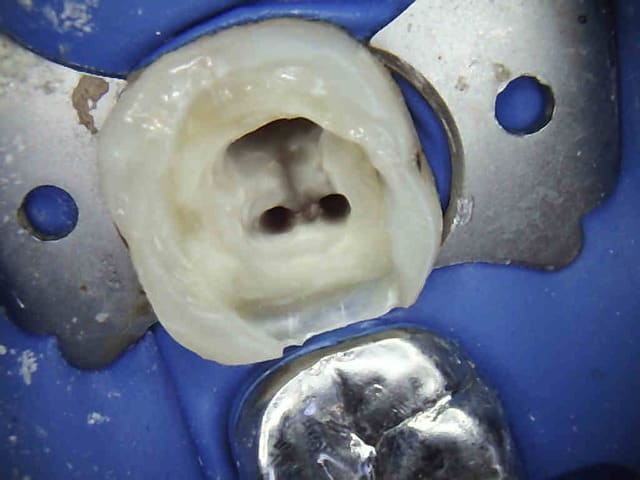

Dis donc le mutualiste tu poses la digue de temps en temps ? ou le fait de faire des tarifs de cerams au raz des pâquerettes t'en empêche ? Ou ton directeur socialiste ne veut pas ?

Tiens mon choupinet mutualiste.-))))

J'y travaille pour trouver un moyen simple et efficace pour poser la digue dans toutes les situations comme celle ci dessous. Tiens c'est tout frais, endo sc33 en 1 temps, 1H 15 et encore je n'ai pas d'assistante au fauteuil.

Pulpite indication endo. perte de substance: Indication onlay , mais pas dans le panier de soins donc sc 33, couronne coulée : patiente CMU.